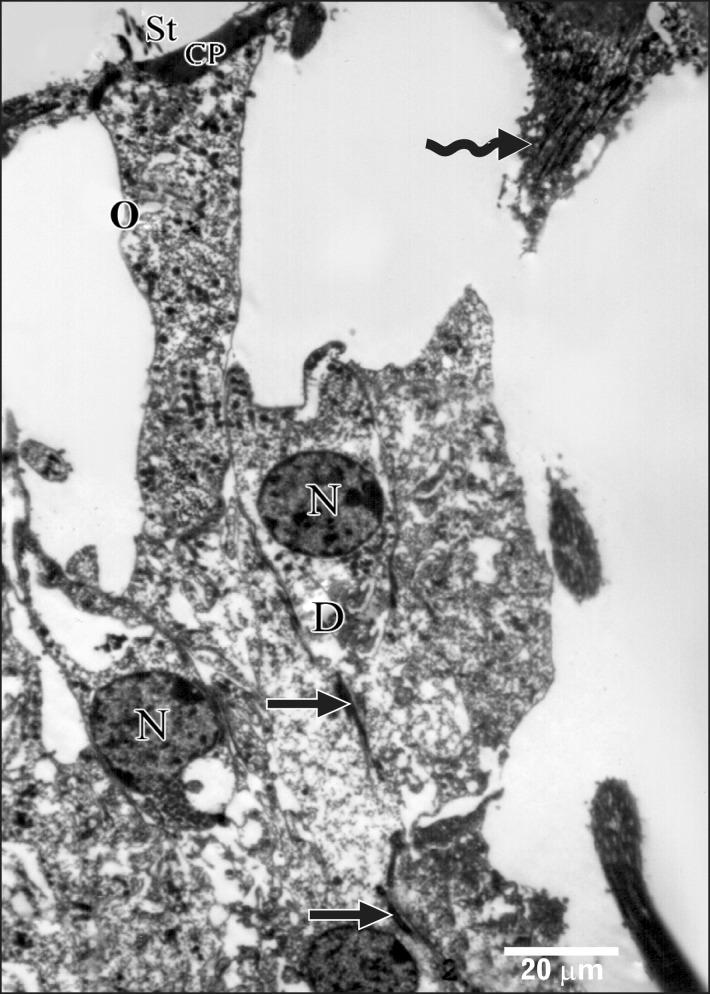

Smoking has been positively associated with hearing loss in human. However, its effect on the cochlea has not been previously evaluated. Aim of work is to investigate the effect of nicotine, which is the primary pharmacological component of tobacco, on the structure of the cochlea of adult male guinea pigs. Fifteen male guinea pigs were classified into two groups: group I (control) and group II (nicotine treated group). Group II was further subdivided into two subgroups; IIA and IIB according to the dose of nicotine (3 mg/kg and 6 mg/kg, respectively). The cochlea was harvested and processed for light microscopy, transmission electron microscopy and scanning electron microscopy. Nicotine administration induced damage of outer hair cells which were distorted in shape with vacuolated cytoplasm and heterochromatic nuclei. Topography revealed damage of the stereocilia which included disorganization, bent and limp or complete loss and expansion of the surrounding supporting cells. These changes were more pronounced in the basal turn of the cochlea and mainly involved the outer hair cells. High dose induced more damage and resulted in protrusion of the apical poles of hair cells (blebing), particularly the outer two rows. Nicotine is proved to be harmful to the cells of the cochlea, particularly the outer hair cells of the basal turn. High doses induce blebing of hair cells.